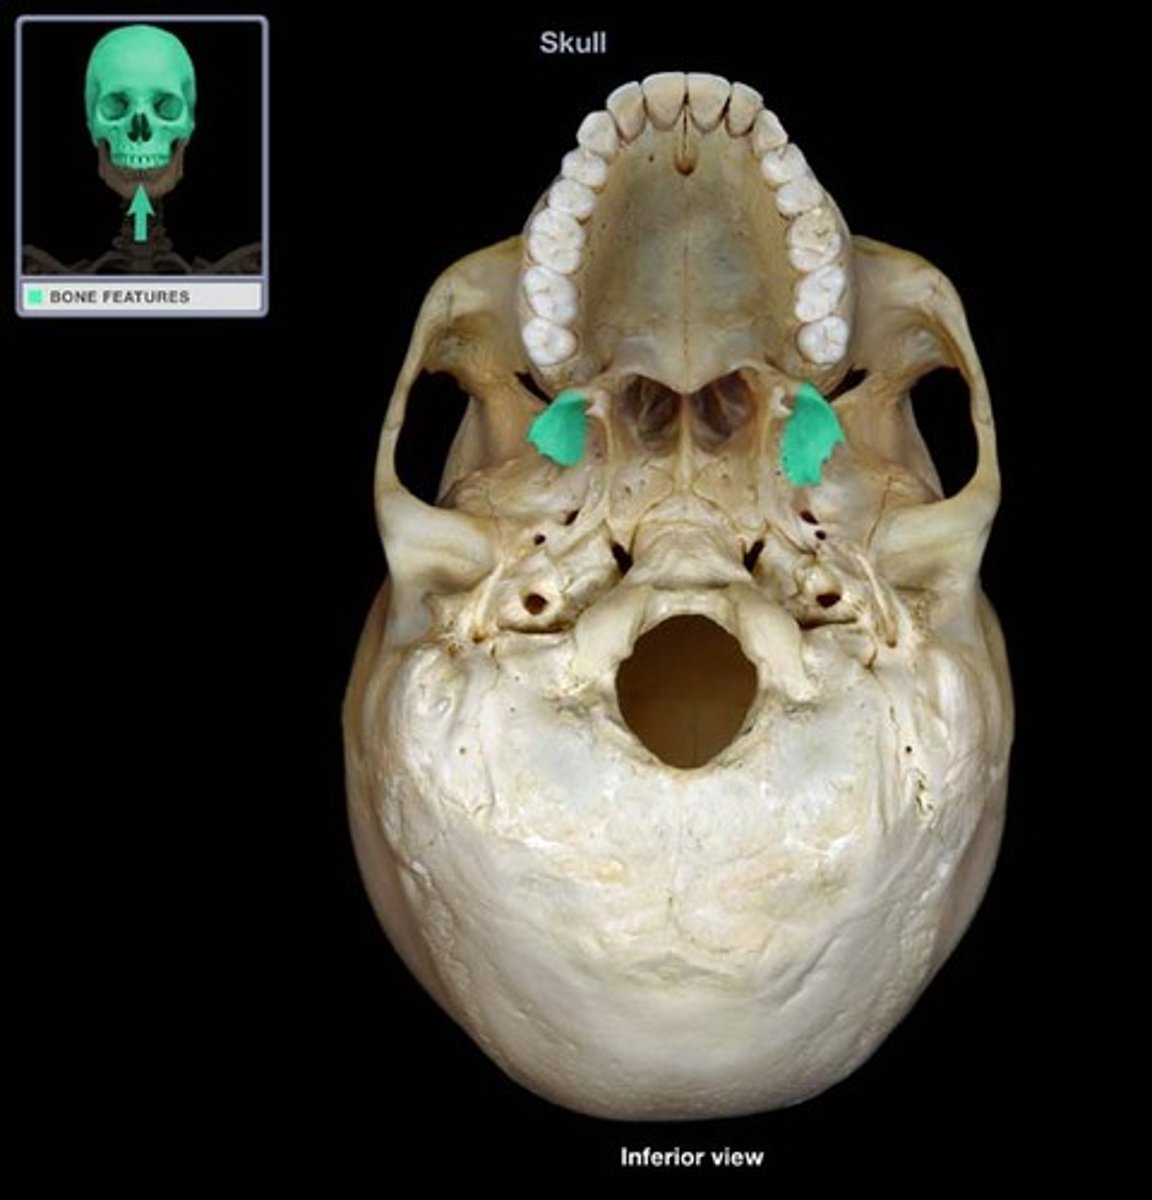

Palatine Bones

Form the anterior part of the hard palate of the mouth and the floor of the nose